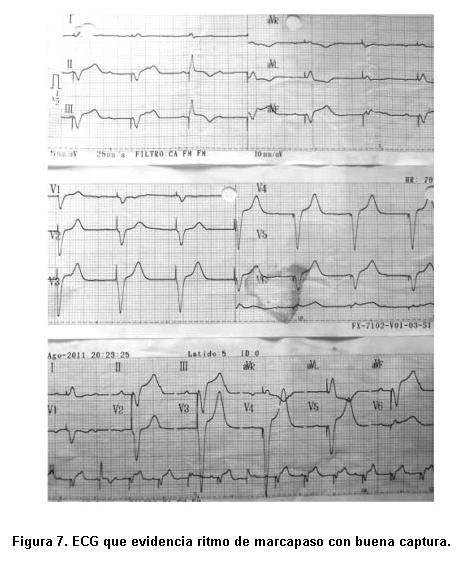

Se interpreta como una embolia séptica a punto de partida de endocarditis infecciosa, por lo que no se realiza angioplastia coronaria y se solicita consulta con equipo de cirugía cardíaca. Estando en sala de hemodinamia se coloca con éxito, por acceso femoral derecho, marcapaso percutáneo transitorio (figura 7).